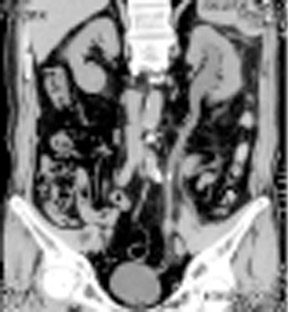

新病院移転と共に、80列マルチスライスCTを導入しました。以前の装置より広範囲をより速く撮影する事ができ、胸部撮影で約5秒、腹部撮影で約10秒の息止めにて撮影出来ます。また、最新の画像処理により以前より少ない被ばく線量にて検査を受ける事が出来るようになりました。

細かいスライスで撮影するため小さな結石でも容易に発見ができ、正確な位置情報を診断する事が出来ます。

従来の輪切りの画像だけではなく、さまざまな方向からの断面像や画像解析装置による診断に有効な3D(立体)表示をして臓器(主に腎臓・前立腺・膀胱)や病巣の大きさ・形状を把握する事が出来ます。造影剤を使用しながら撮影する事により、より鮮明な画像が得られます。